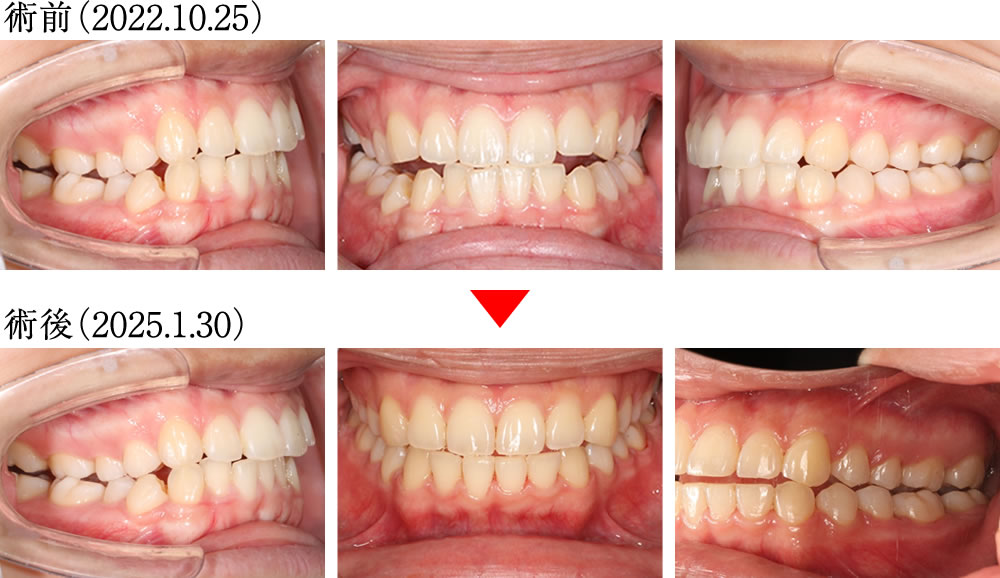

術前は上下顎の正中がずれており、右側に咬合不良が見られる歯並びでした。しかし術後は上下の正中がしっかりと揃い、理想的な被蓋関係で噛める、きれいで安定した歯並びへと改善しました。

術前は歯が重なり合うように乱れた歯並びでしたが、術後は歯が理想的に整列し、きれいで大きなアーチを形成する歯並びへと改善しました。